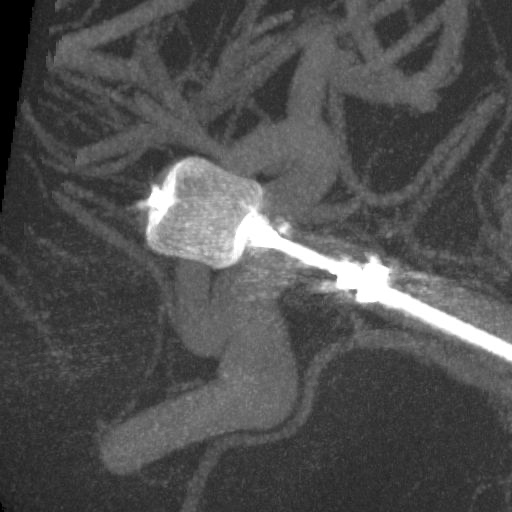

当院では必要に応じて脳血管内治療(IVR)も行います。

脳動脈瘤のコイル塞栓術や、脳血管の狭窄に対するステント留置術など、IVR(インターベンショナル・ラジオロジー:)と呼ばれる血管内治療に対応しています。

脳血管内治療WovenEndoBridgeデバイス(WEB)